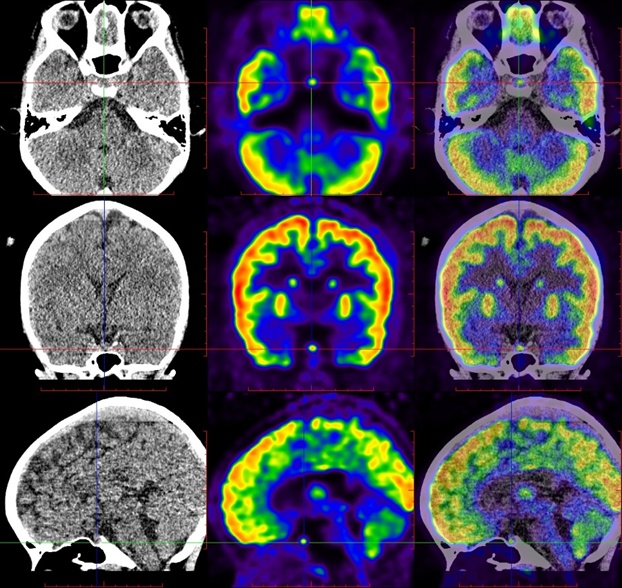

于是,新华医院核医学科第一时间给悠悠做了全身PET/CT检查,评估全身情况,垂体内肿物是否恶性肿瘤,全身其他部位还有没有累及。检查结果令大家大跌眼镜,原来悠悠不仅脑垂体有个FDG高摄取的肿物,她的右侧髂骨和左侧第10肋骨都出现了明显骨质破坏和FDG摄取增高。

图1:垂体隆起的FDG高代谢肿物

图2:左侧第10后肋(黄箭),右侧髂骨(白箭)骨质破坏伴FDG高代谢病灶